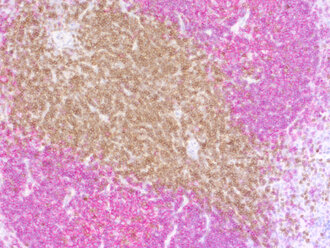

Double-staining of CD3e positive T-cells and CD19 positive B-cells in FFPE mouse spleen section

IHC-P: 1 : 100 gallery